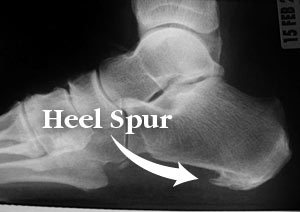

Heel spurs are bony outgrowths positioned where the plantar fascia tissue attaches to the heel bone (the calcaneus). Heel spurs seldom cause pain. It is the inflamed tissue surrounding the spur that causes the pain. The Latin meaning of Plantar Fasciitis is, “Inflammation of Plantar Fascia.” The plantar fascia is a long, thick and very tough band of tissue beneath your foot that provides arch support. It also connects your toes to your heel bone. Each time you take a step, the arch slightly flattens to absorb impact. This band of tissue is normally quite strong and flexible but unfortunately, circumstances such as undue stress, being overweight, getting older or having irregularities in your foot dynamics can lead to unnatural stretching and micro-tearing of the plantar fascia. This causes pain and swelling at the location where the plantar fascia attaches to the heel bone. As the fascia continually pulls at the heel bone, the constant irritation eventually creates a bony growth on the heel. This is called a heel spur.

Definition: Heel Spur (Calcaneal spur)